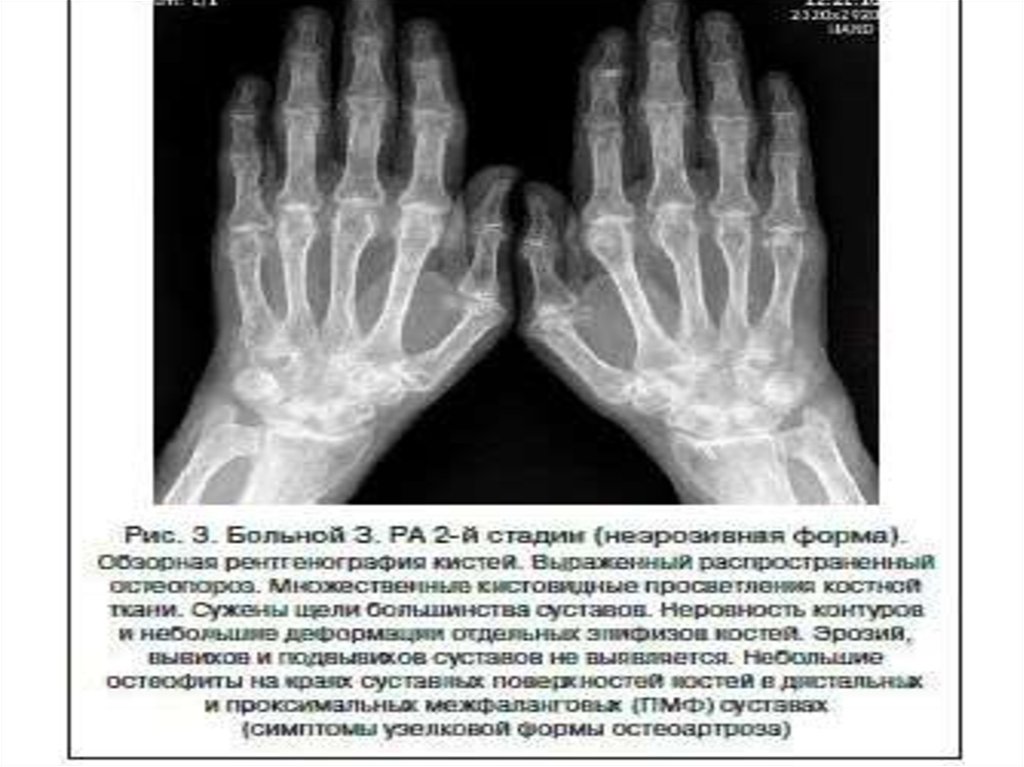

Рентгенодиагностика артрита

1. Рентгенодиагностика артрита